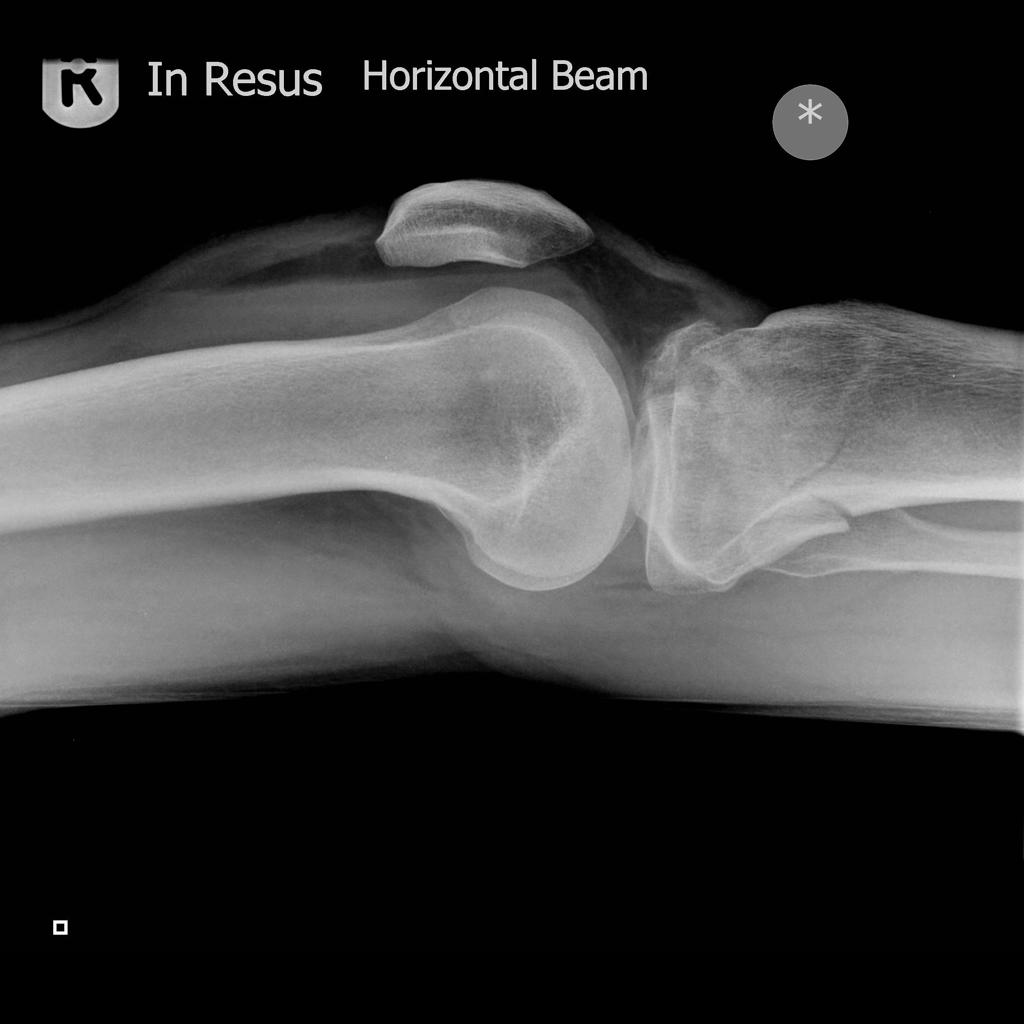

A lipoheamarthrosis describes layering of less radiodense fat on top of the more radiodense blood, in the same way that less dense oil will float on top of more dense water. This layering is appreciable on horizontal beam lateral projections as a discrete layer-line within the effusion.

On occasion, a lipohaemarthrosis can appear as multiple layers, with a somewhat stripy appearance if the patient’s knee has not been supine for enough time for the components to separate fully, usually taking a couple of minutes or so.

The presence of a lipohaemarthrosis is pathognomonic for intra-articular bony injury; if no bony injury can be seen, further plain film views or a cross-sectional study may be required to diagnose the occult injury and inform management.

PRACTICAL POINT: when sending your HBL knee to PACS, ensure that the image is orientated as above, with the anterior/superior aspects to the left/right. Some radiographers and reporters prefer to view HBLs orientated longitudinally – this is largely a hangover from the bad old days of making multiple exposures on one physical film to save money and, in the opinion of opinionated people who run websites, has no place in the modern world of computed/digital radiography.

To confidently exclude the presence of a lipohaemarthrosis, the reporter must be certain that the image was taken horizontal beam. This means annotating and sending images correctly orientated.